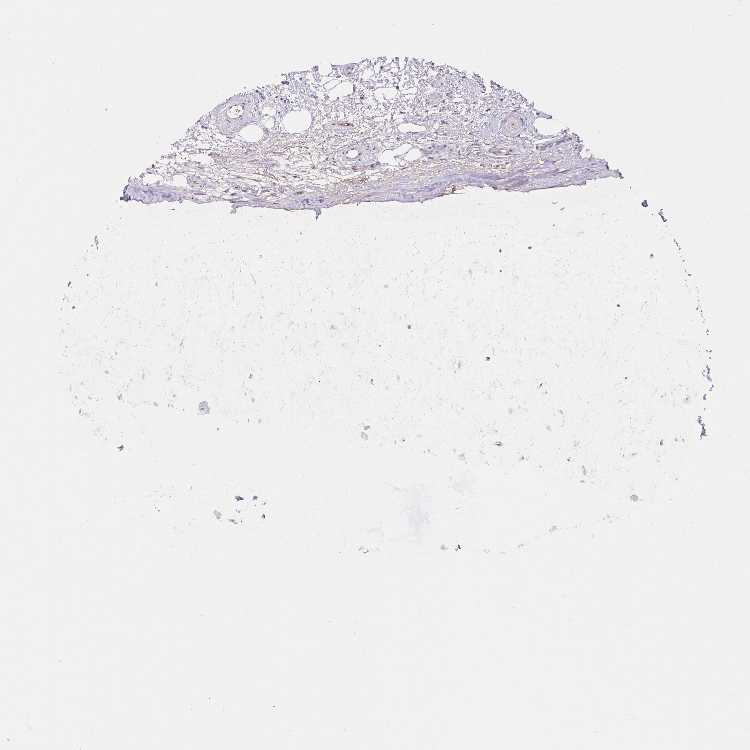

ADIPOSE TISSUE - Antibody stainingi

Antibody staining in the annotated cell types in the current human tissue is reported as not detected, low, medium, or high, based on conventional immunohistochemistry profiling in selected tissues. This score is based on the combination of the staining intensity and fraction of stained cells.

Each image is clickable and will lead to virtual microscopy that enables deeper exploration of all samples and also displays staining intensity scores, fraction scores and subcellular localization as well as patient and tissue information for each sample.

Antibody HPA027529Antibody HPA074638Antibody CAB033120

Adipocytes Not detectedMediumLow